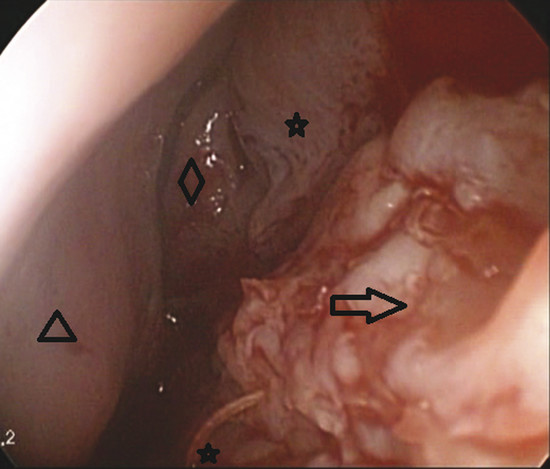

At this point an endoscope (0 degree, 4 mm) is used. The edge of the perforation is incised superiorly, posteriorly, and inferiorly using a number 12 scalpel blade, and a tunnel is created by dissecting between the mucoperichondrium of both sides and between the mucoperichondrium and the septal cartilage on the one side (Fig. 9‑1).

A partial inferior turbinectomy is performed. The inferior turbinate graft is then flattened, taking care not to disturb its continuity (Fig. 9‑2).

Vicryl 4/0 sutures are used to fix the graft in place within the tunnel. The first stitch is made posteriorly by taking one bite about 5 mm posterior to the posterior edge of the perforation and the other bite into the graft. The graft is then approximated to the perforation and tucked into place as the stitch is tightened (Fig. 9‑3).

The graft is positioned between the mucoperichondrium of both sides and between the mucoperichondrium and the cartilage of the one side. The graft is fixed by more stitches positioned superiorly, inferiorly, and anteriorly (Fig. 9‑4, Fig. 9‑5).